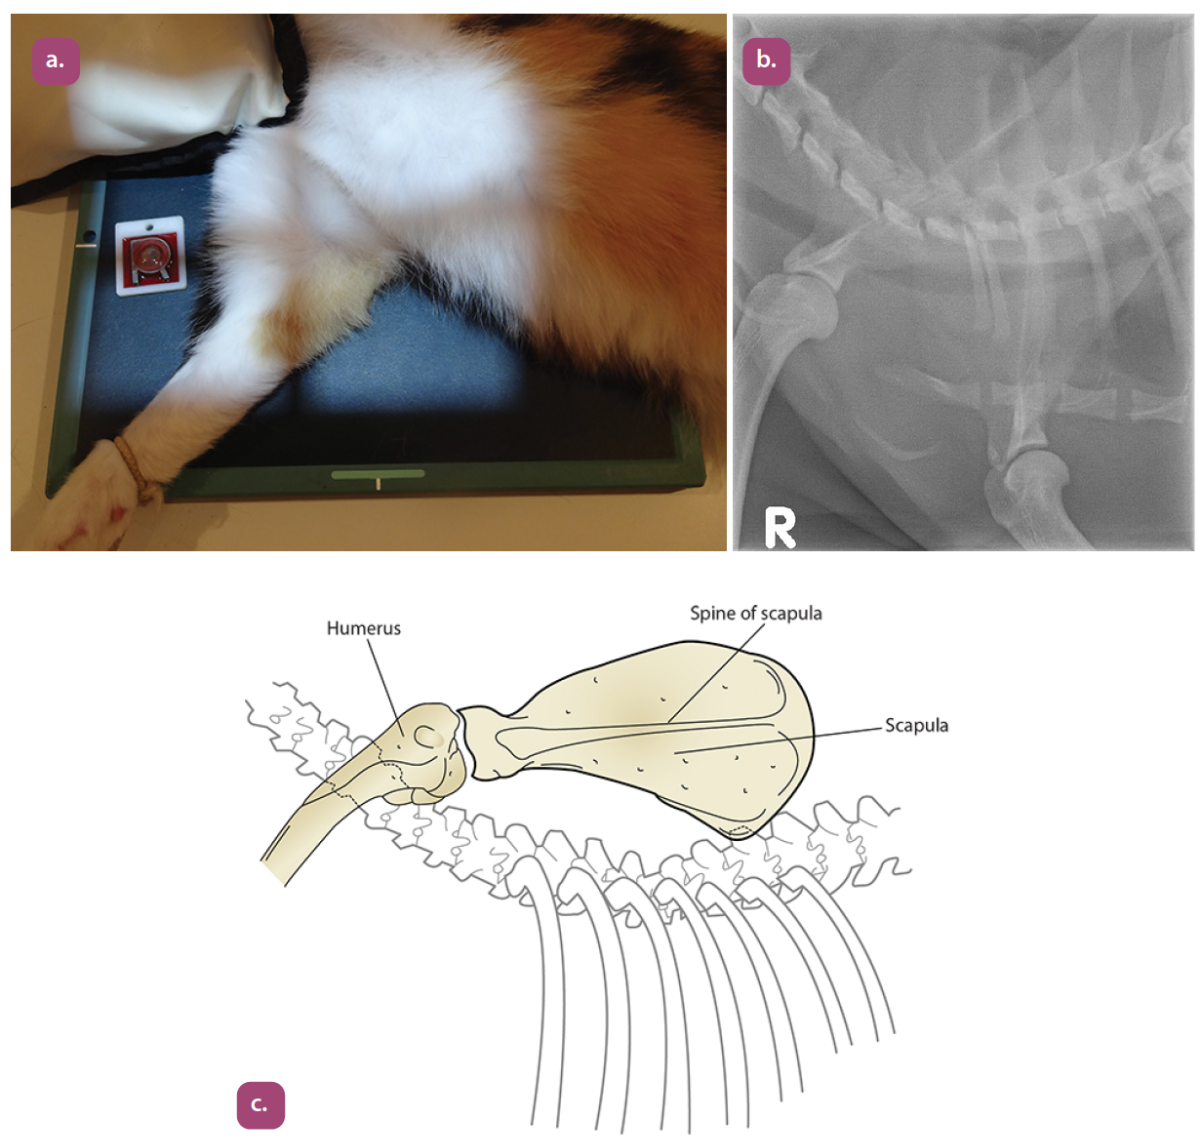

lateral projection of the scapula

caudocranial projection of the scapula